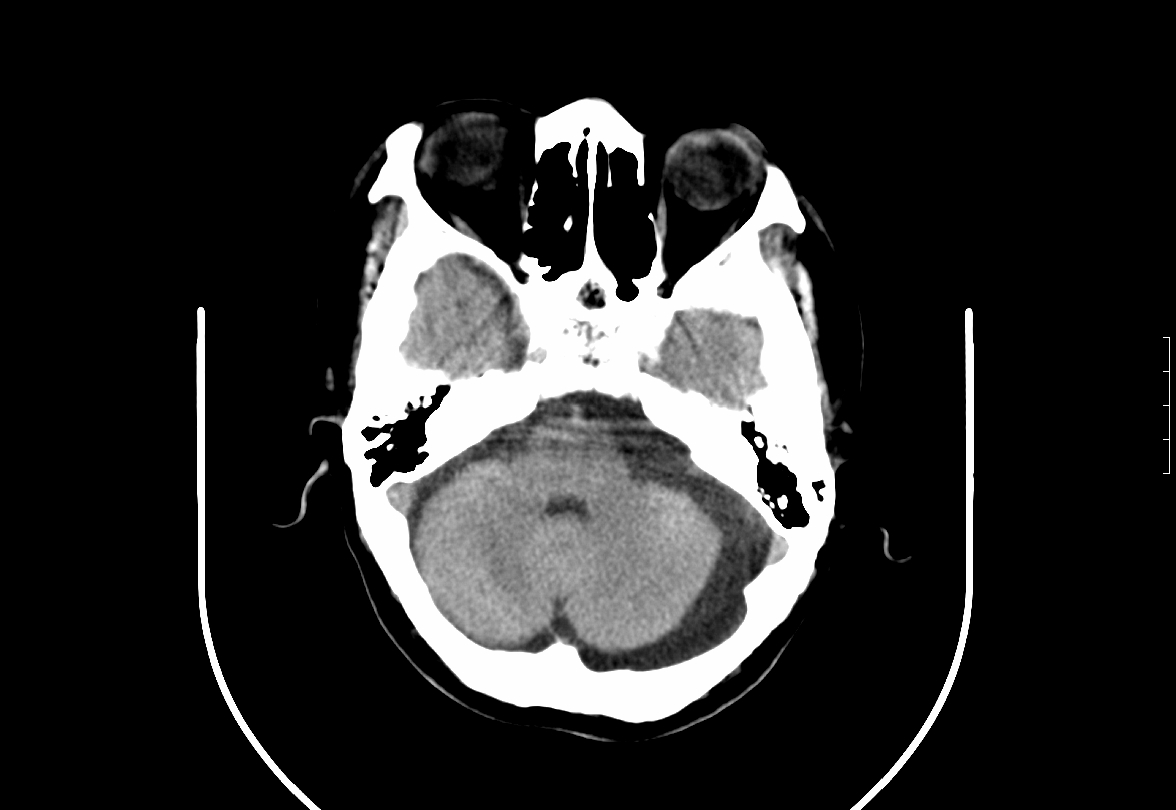

CT50272:男.65Y,头晕4月余。否认有外伤史。

本帖最后由 cefcmj 于 2015-4-14 15:20 编辑 病理体征未引出,血压不高。血肿?脑膜瘤?请会诊

慢性硬膜外血肿伴机化

慢性硬膜下血肿并慢性活动性出血

支持,慢性硬膜外血肿伴机化。

硬膜外血肿

慢性硬膜外血肿伴机化及大脑镰下疝

这人胼胝体咋这样?左侧慢性硬膜外血肿伴机化支持。